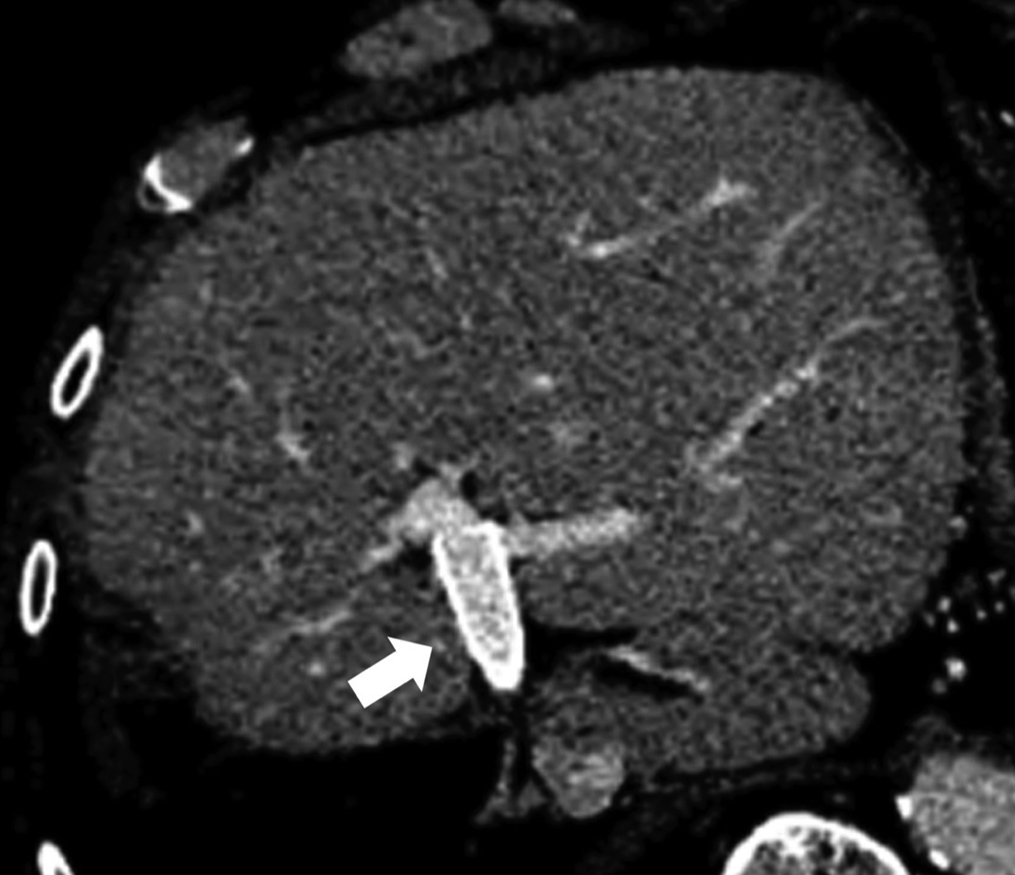

退院後は2か月ごとのD-dimerを含めた採血検査と,6か月ごとの腹部造影CTで経過観察している.現在術後13か月経過したが,血栓を形成することなく門脈血流は開存を認めている(Fig. 5).

Abdominal enhanced CT at 13 months after surgery shows patent portal vein stent (arrow).